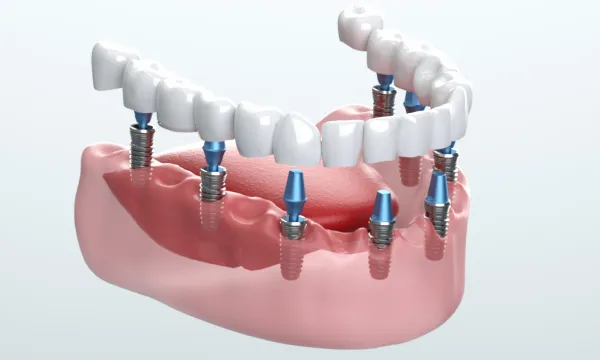

All-on-4/6とは?少ない本数で

全体を支える新しい治療

Supporting Mechanism片顎4~6本で

12本相当を支える仕組み

オールオンフォー/シックスでは、奥歯のインプラントを斜めに埋入する独自の方法を採用します。これにより骨のある部分を有効に使い、片顎4~6本という少ない本数で全体を支えることが可能になります。

従来の治療では歯を失った本数に近い数のインプラントを必要とすることが多く、骨移植や大がかりな骨造成を伴うケースも少なくありませんでした。これに対しオールオンフォー/シックスは、骨の状態を最大限活かしながら安定した支持を得られるのが大きな特徴です。

さらに、インプラントは骨と結合する性質があるため、強固な土台として機能します。その上に装着する人工歯は色や形を調整でき、自然で快適な仕上がりを目指せます。